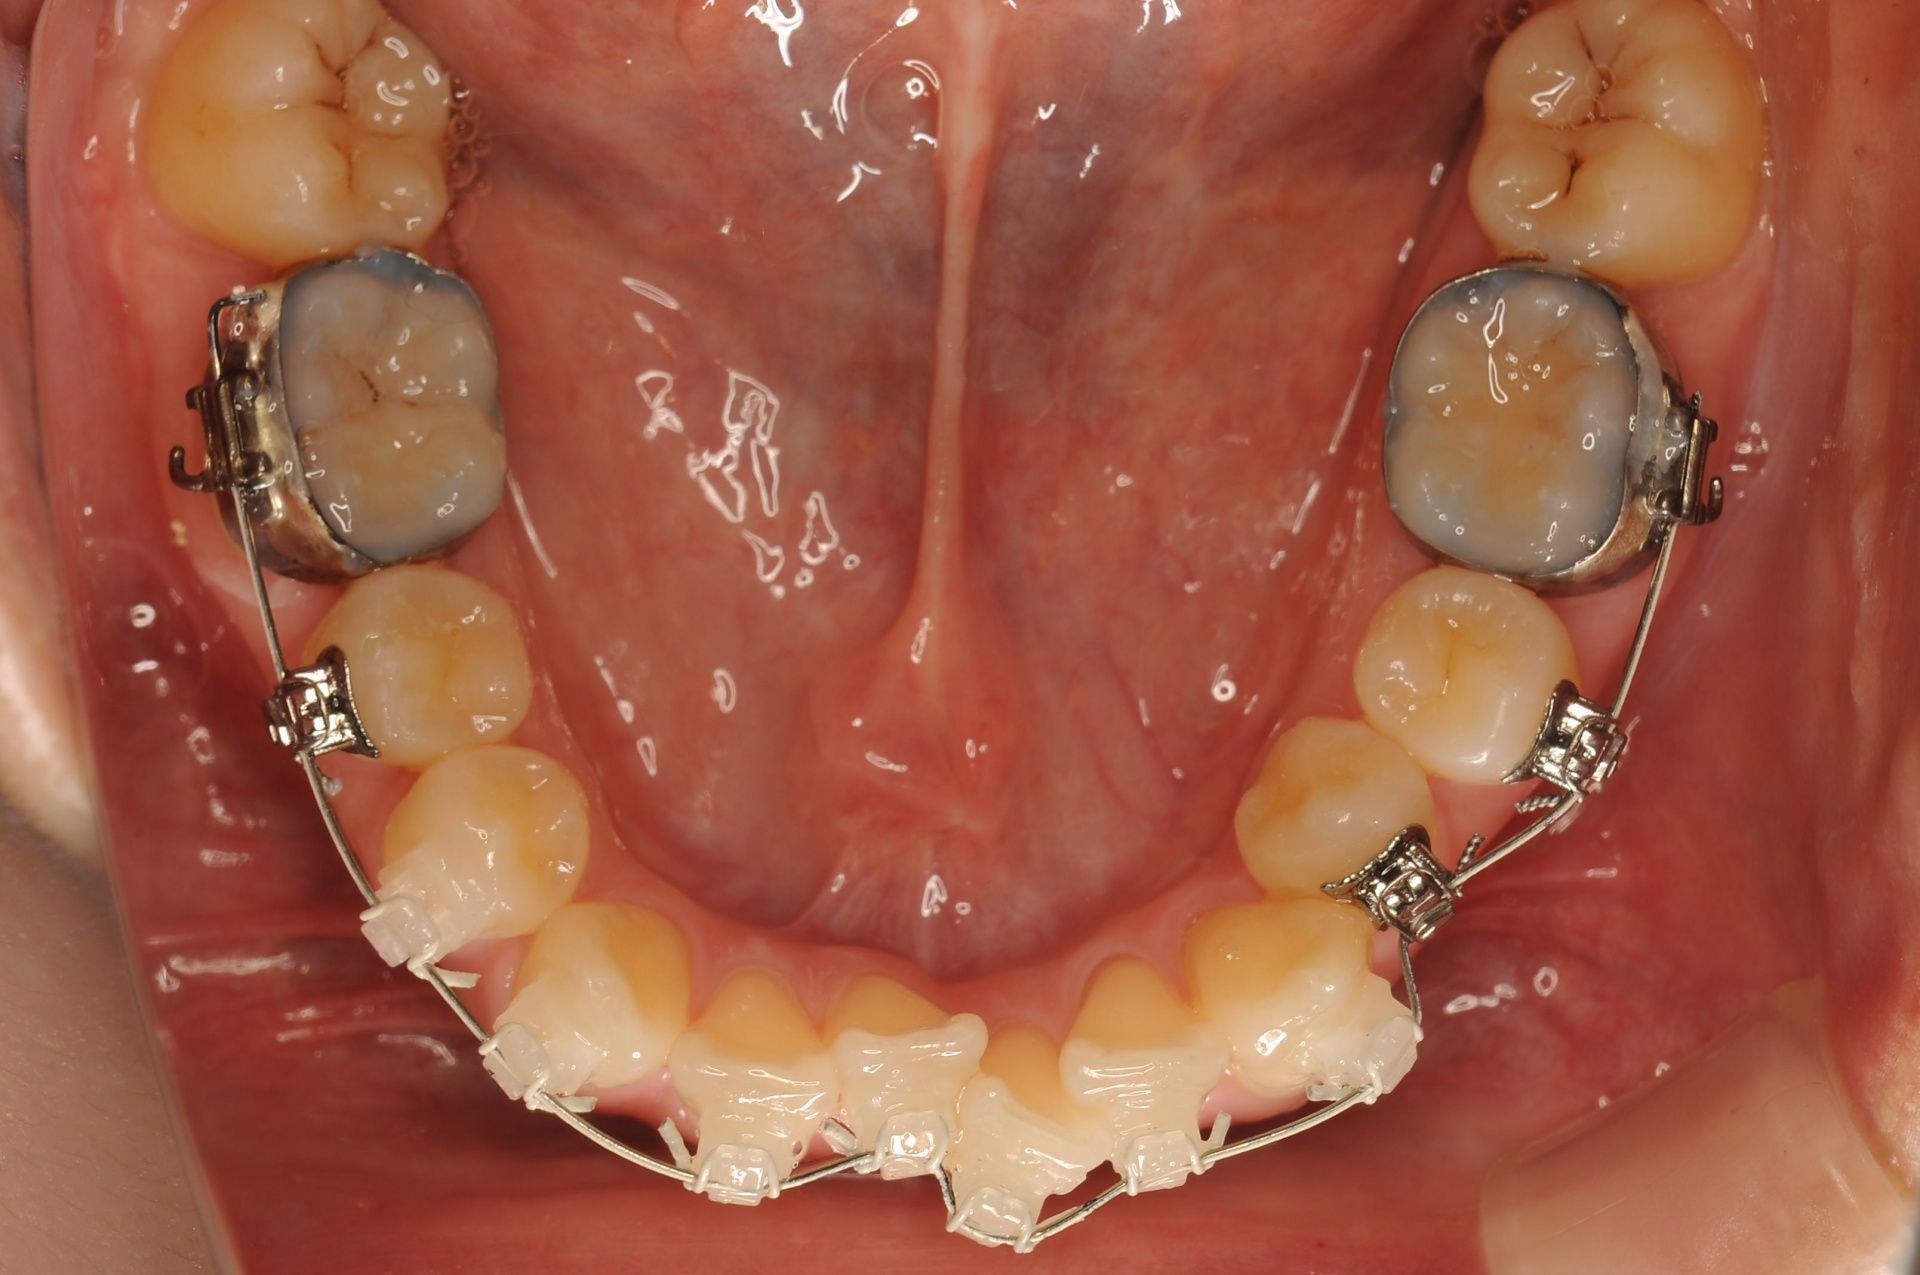

治療中

見えない装置(裏側矯正)を希望されましたので、上顎は裏側に装置をつけて、下顎はセラミックの白い装置としました。上顎両側犬歯を小臼歯の抜歯したスペースへ移動させました。下顎は非抜歯で叢生を改善しました。